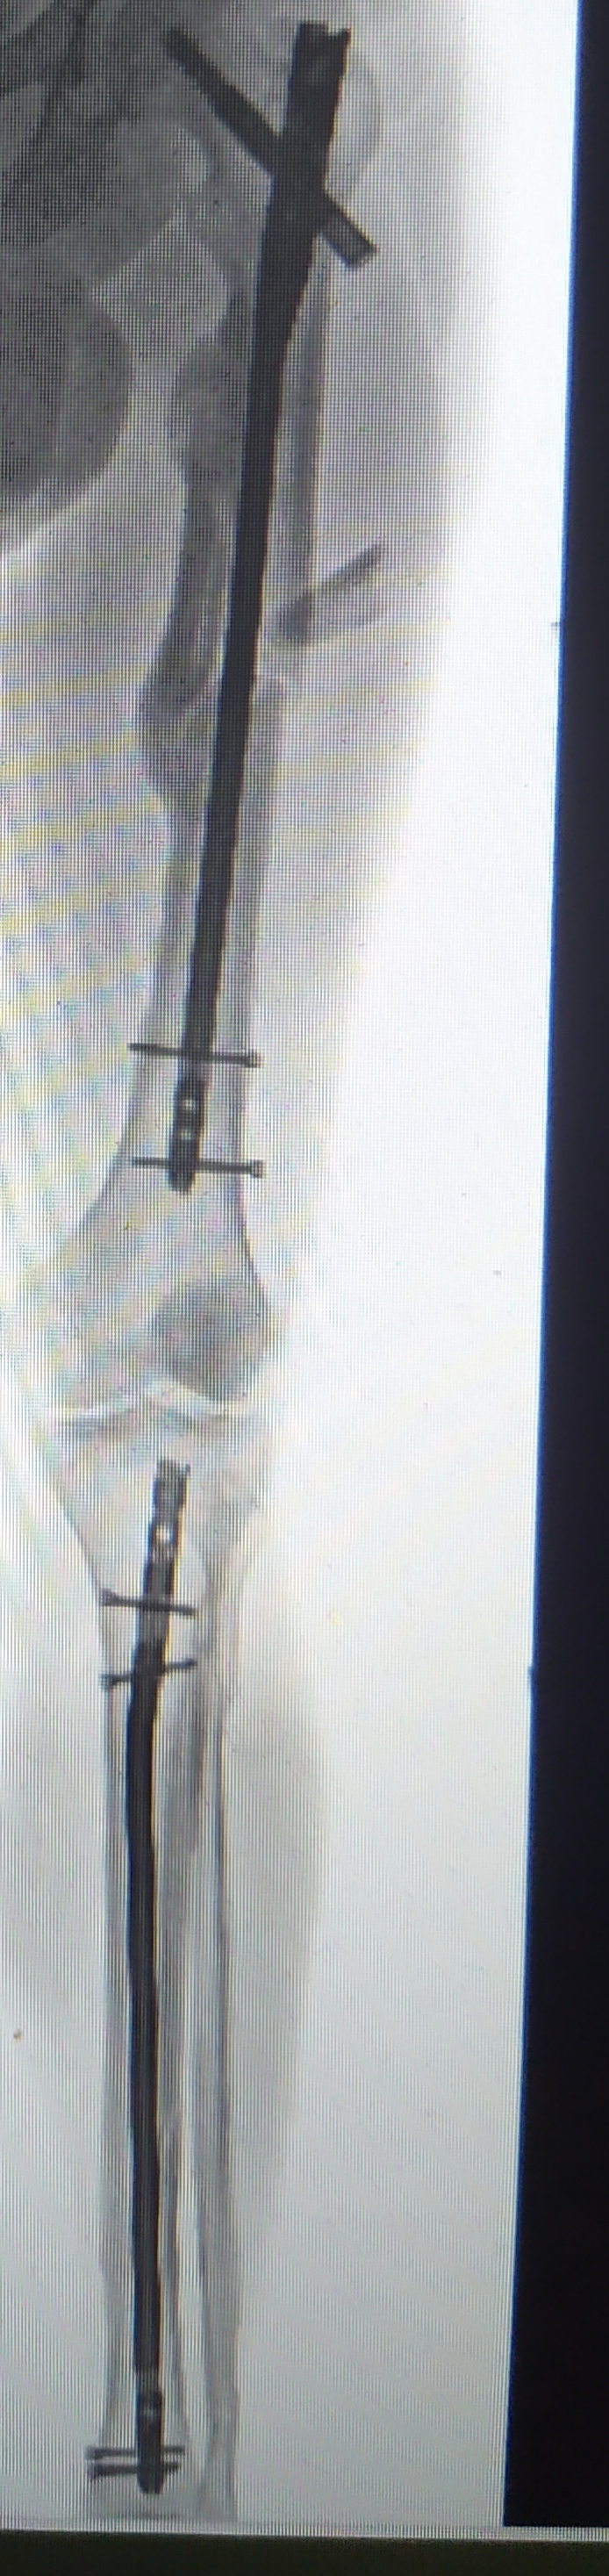

У меня оскольчатый фрагментарный перелом диафиза бедра со смещением отломков. Шрамов теперь ояебу. Помимо шрама на ноге, шрам от полостной операции на животе, страшенные шрамы на коленях, на плече, на боках. Так что, у тебя ещё не так всё плохо:) мне всё тело забивать тату придётся